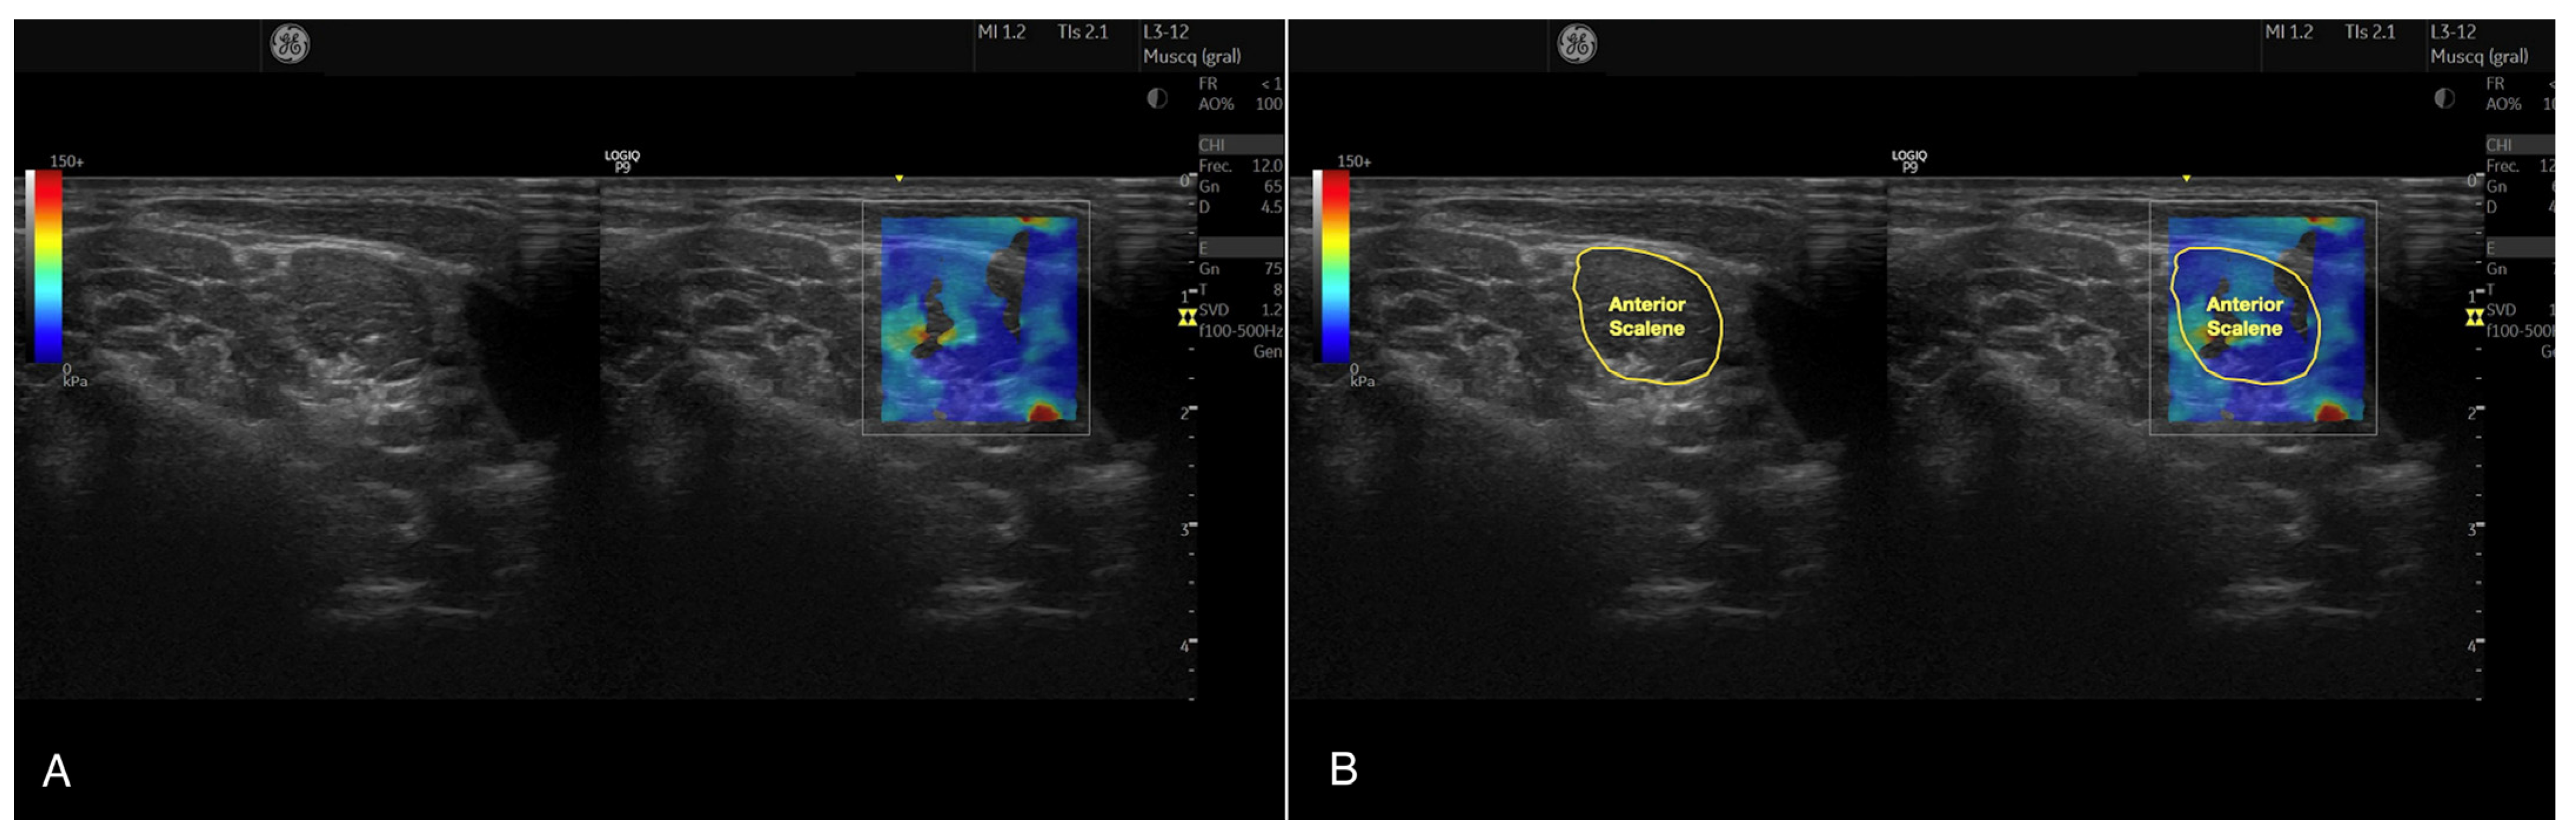

2.4.2. Anterior Scalene Muscle Stiffness

- Valera-Calero, J.A.; Gómez-Sánchez, S.; Fernández-de-Las-Peñas, C.; Plaza-Manzano, G.; Sánchez-Jorge, S.; Navarro-Santana, M.J. A Procedure for Measuring Anterior Scalene Morphology and Quality with Ultrasound Imaging: An Intra- and Inter-rater Reliability Study. Ultrasound Med. Biol. 2023, 49, 1817–1823. [Google Scholar] [CrossRef]